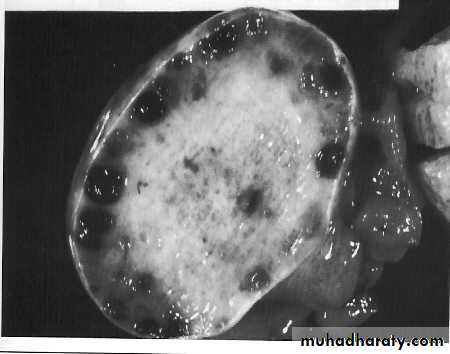

3-p0lycystic ovary syndrome

The other common ovarian disorder leading to anovulation and amenorrhoea is PCOSPituitary disorders

Imaging studies

*Ultrasound:Determine the presence, state and size

of ovaries and any follicular activity.Determine the presence and size of

uterusChromosomal analysis: